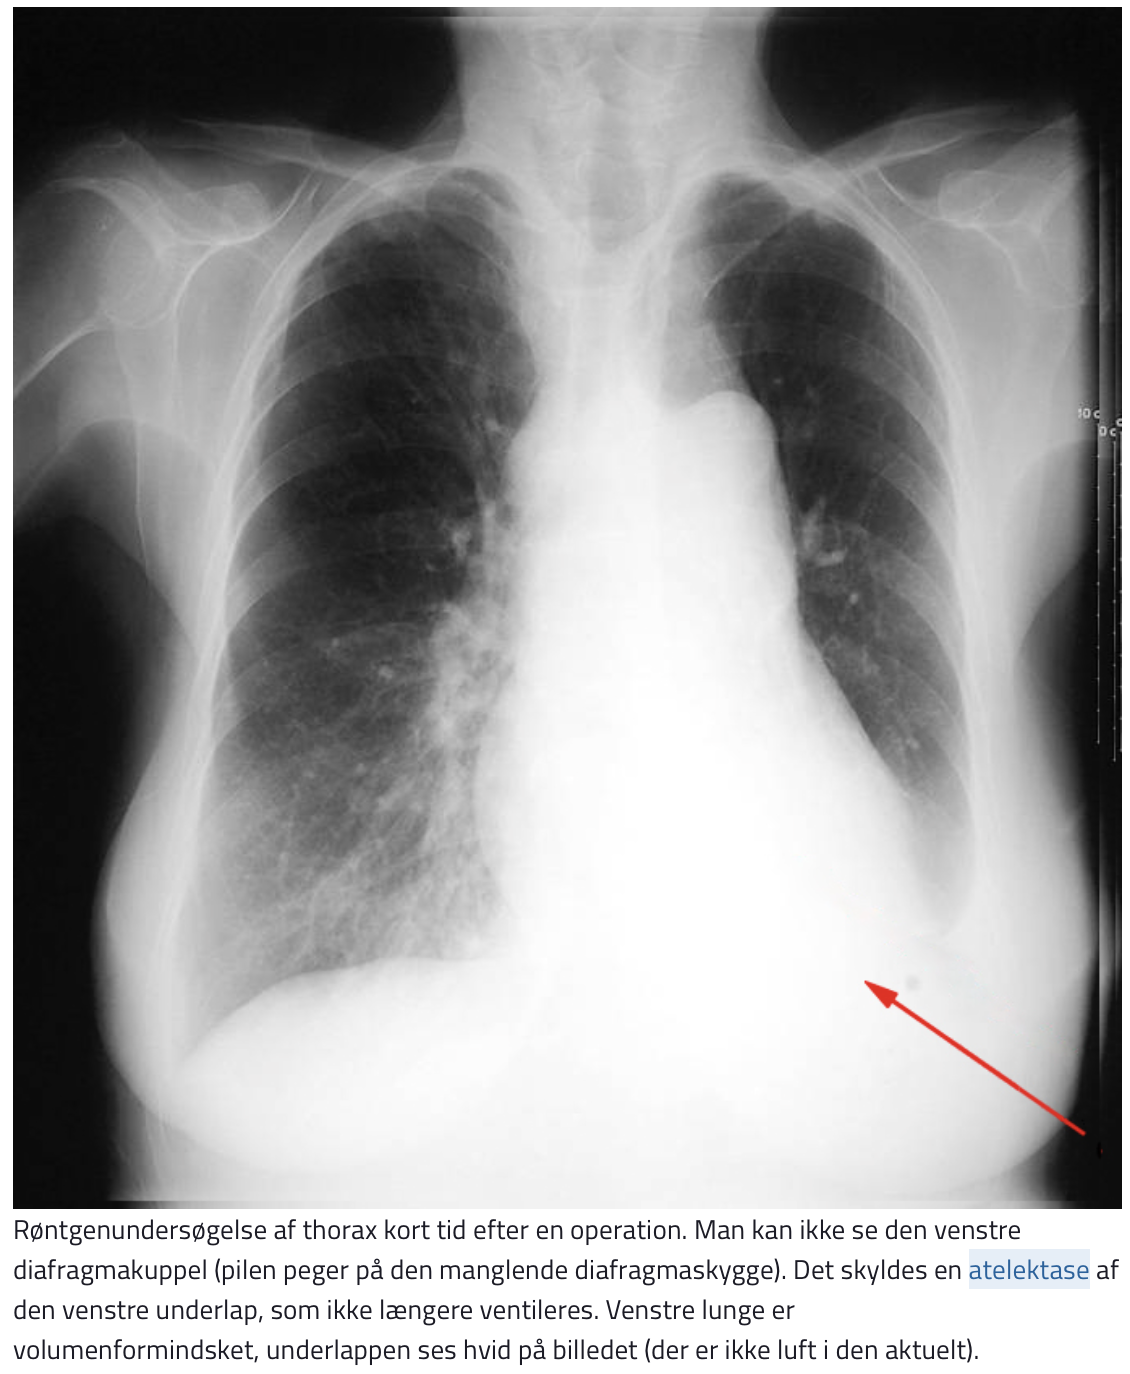

Atelektase:

- Det klassiske billede er en kileformet homogen skygge med spidsen mod hilus – (”unormale linjer”)